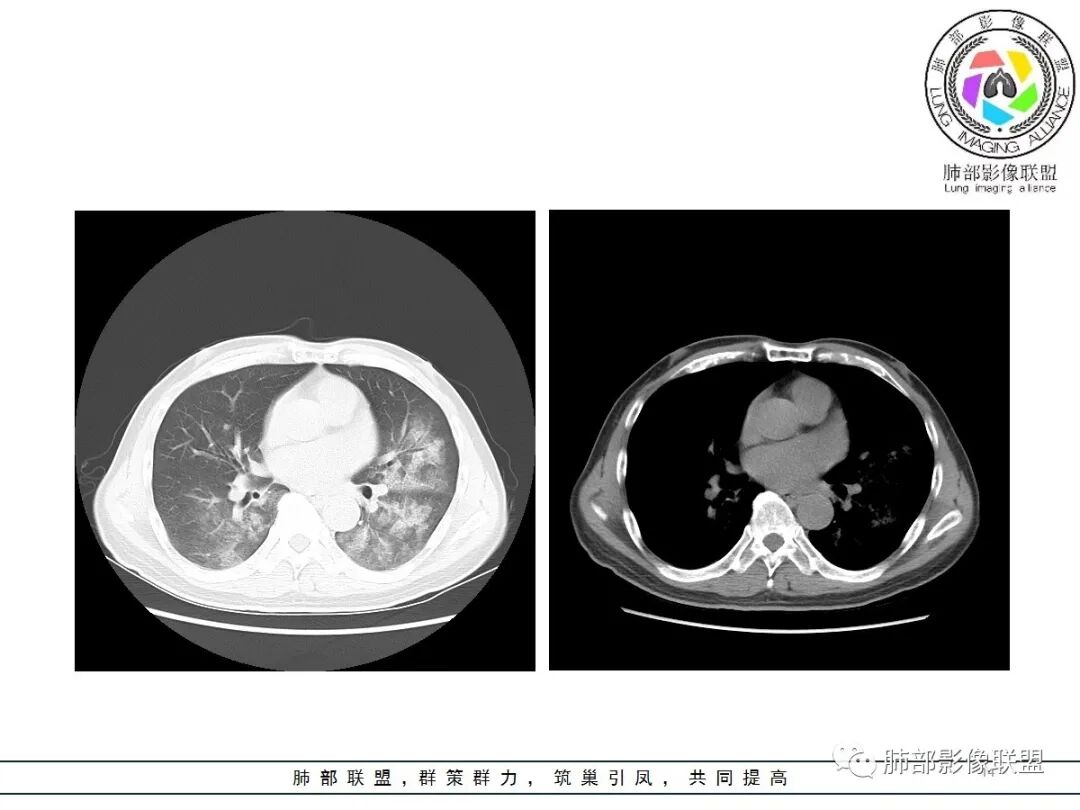

影像:双肺对称性中内带为主分布磨玻璃影,实变不明显。无胸水及小叶间隔增厚。

病史中D2聚体明显升高,影像:双肺对称性中内带为主分布磨玻璃影,有坠积感,实变不明显,胸膜下回避。无胸水及小叶间隔增厚;肺水肿?感染?建议CTPA检查除外肺栓。

CT示双肺中内带多发斑片状磨玻璃影,沿支气管血管束分布,边界模糊,部分支气管壁增厚。定位气道来源的病变,考虑非典型病原体感染,鹦鹉热可能。

男,65,咳嗽、发热1天,黄粘痰,痰中带血。饲养鹦鹉,新冠疫苗第二针后,本地有新冠病例。血像高。胸部CT:双肺中内带多发斑片样磨玻璃影,边缘不清,沿支气管血管束分布,左肺重,细网络,小叶内间隔增厚,支气管充气征。诊断:肺门为中心两侧大概对称GGO,首先考虑DAH(血管炎)?不典型病原体感染,鹦鹉热、病毒待排。鉴别肺水肿、PCP等。

肺水肿影像表现

1.间质性肺水肿:小叶间隔增厚,尚光滑,支气管血管束增粗,肺血管影模糊,胸膜或叶间裂增厚,肺内有磨玻璃密度影,常有重力分布趋势。

2.肺泡性肺水肿 :

(1)中央型分布:以肺门为中心,两肺中内带对称分布的大片状实变,称为“蝶翼征”。常见于心源性及肾源性肺水肿患者。也可表现为磨玻璃密度病灶,弥漫性分布或以小叶中心性分布。

(2)弥漫型肺水肿:弥漫分布于两肺内的多发斑片状磨玻璃密度及实变影,大小和密度不等,可融合成大片状阴影,可见空气支气管征。